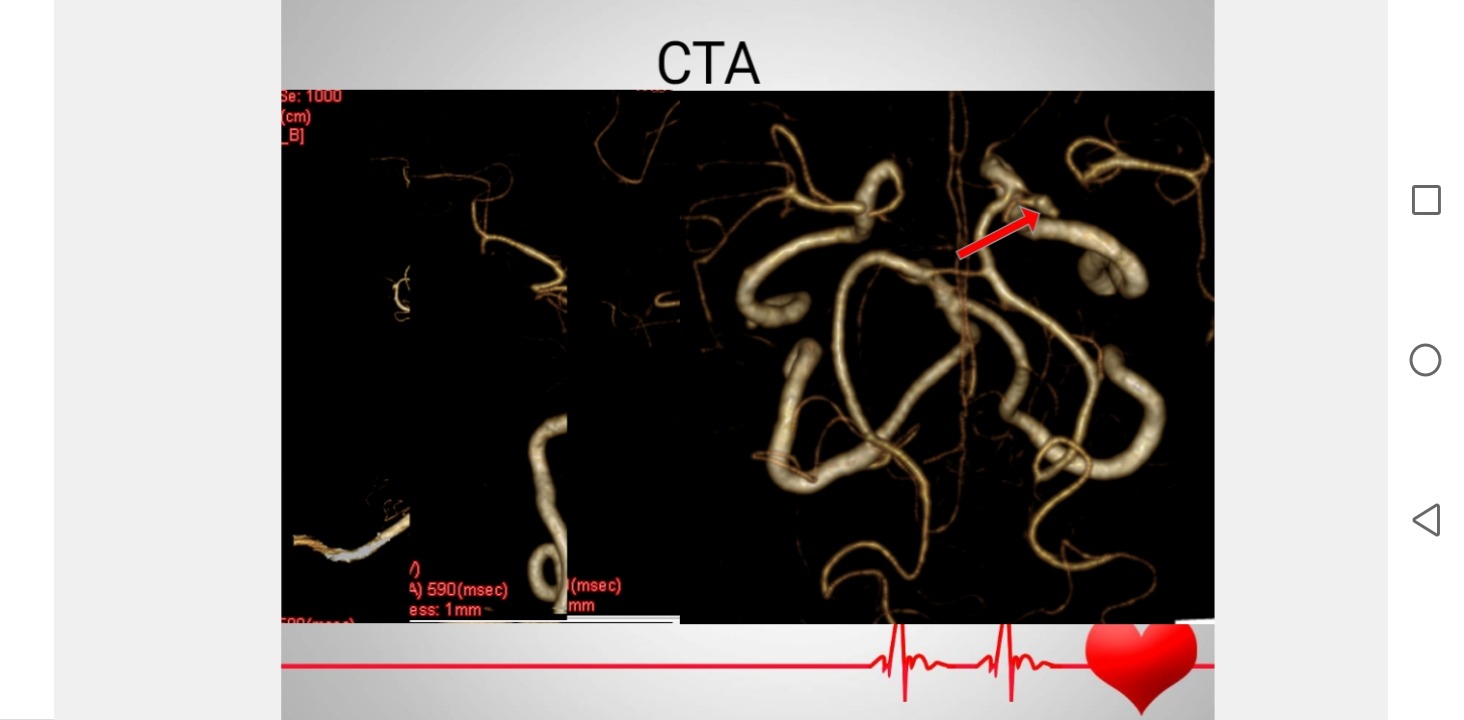

头颅CTA检查提示多发脑血管狭窄,右侧颈内动脉末端假性动脉瘤?